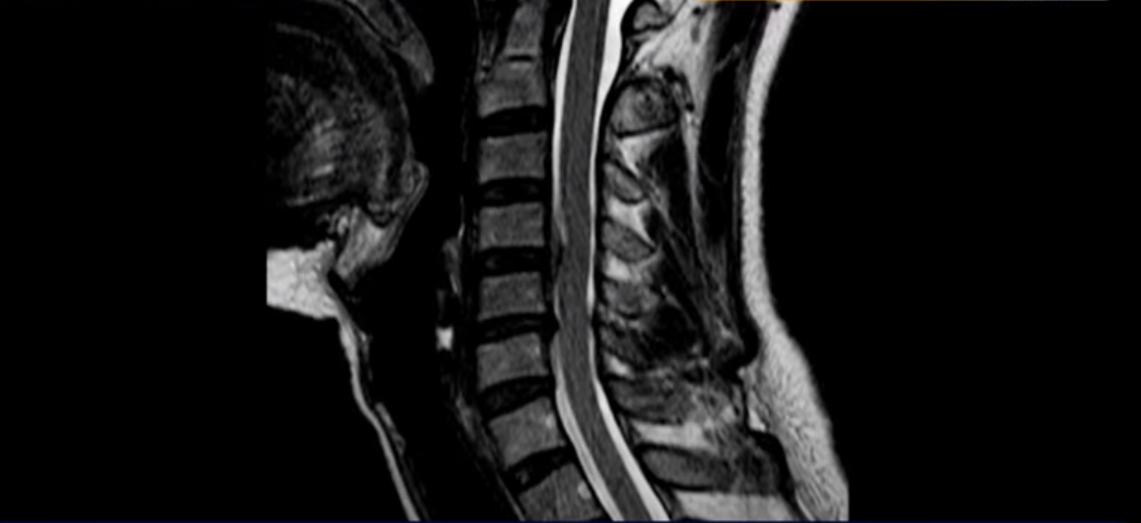

우선 이분 MRI를 보기 전에 이분 증상에 대해 말씀 드리면 오른쪽 팔저림과 방사통 및 어깨 통증이 있습니다. MRI를 보면 4번 5번에 디스크 파열이 보입니다.

밀려나온 디스크가 위로 타고 올라가 있는데 보시다시피 가운데로 밀려 나와 있습니다.